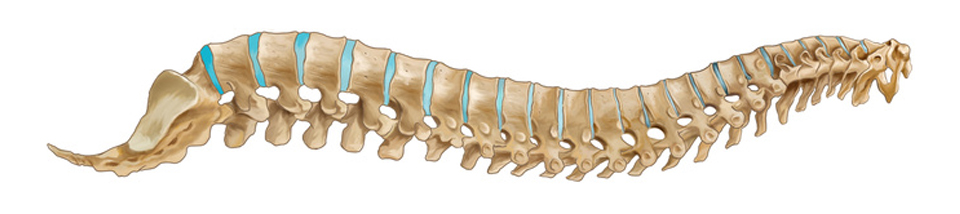

Структура позвоночника: сегменты и тазовые отделы в фотографиях